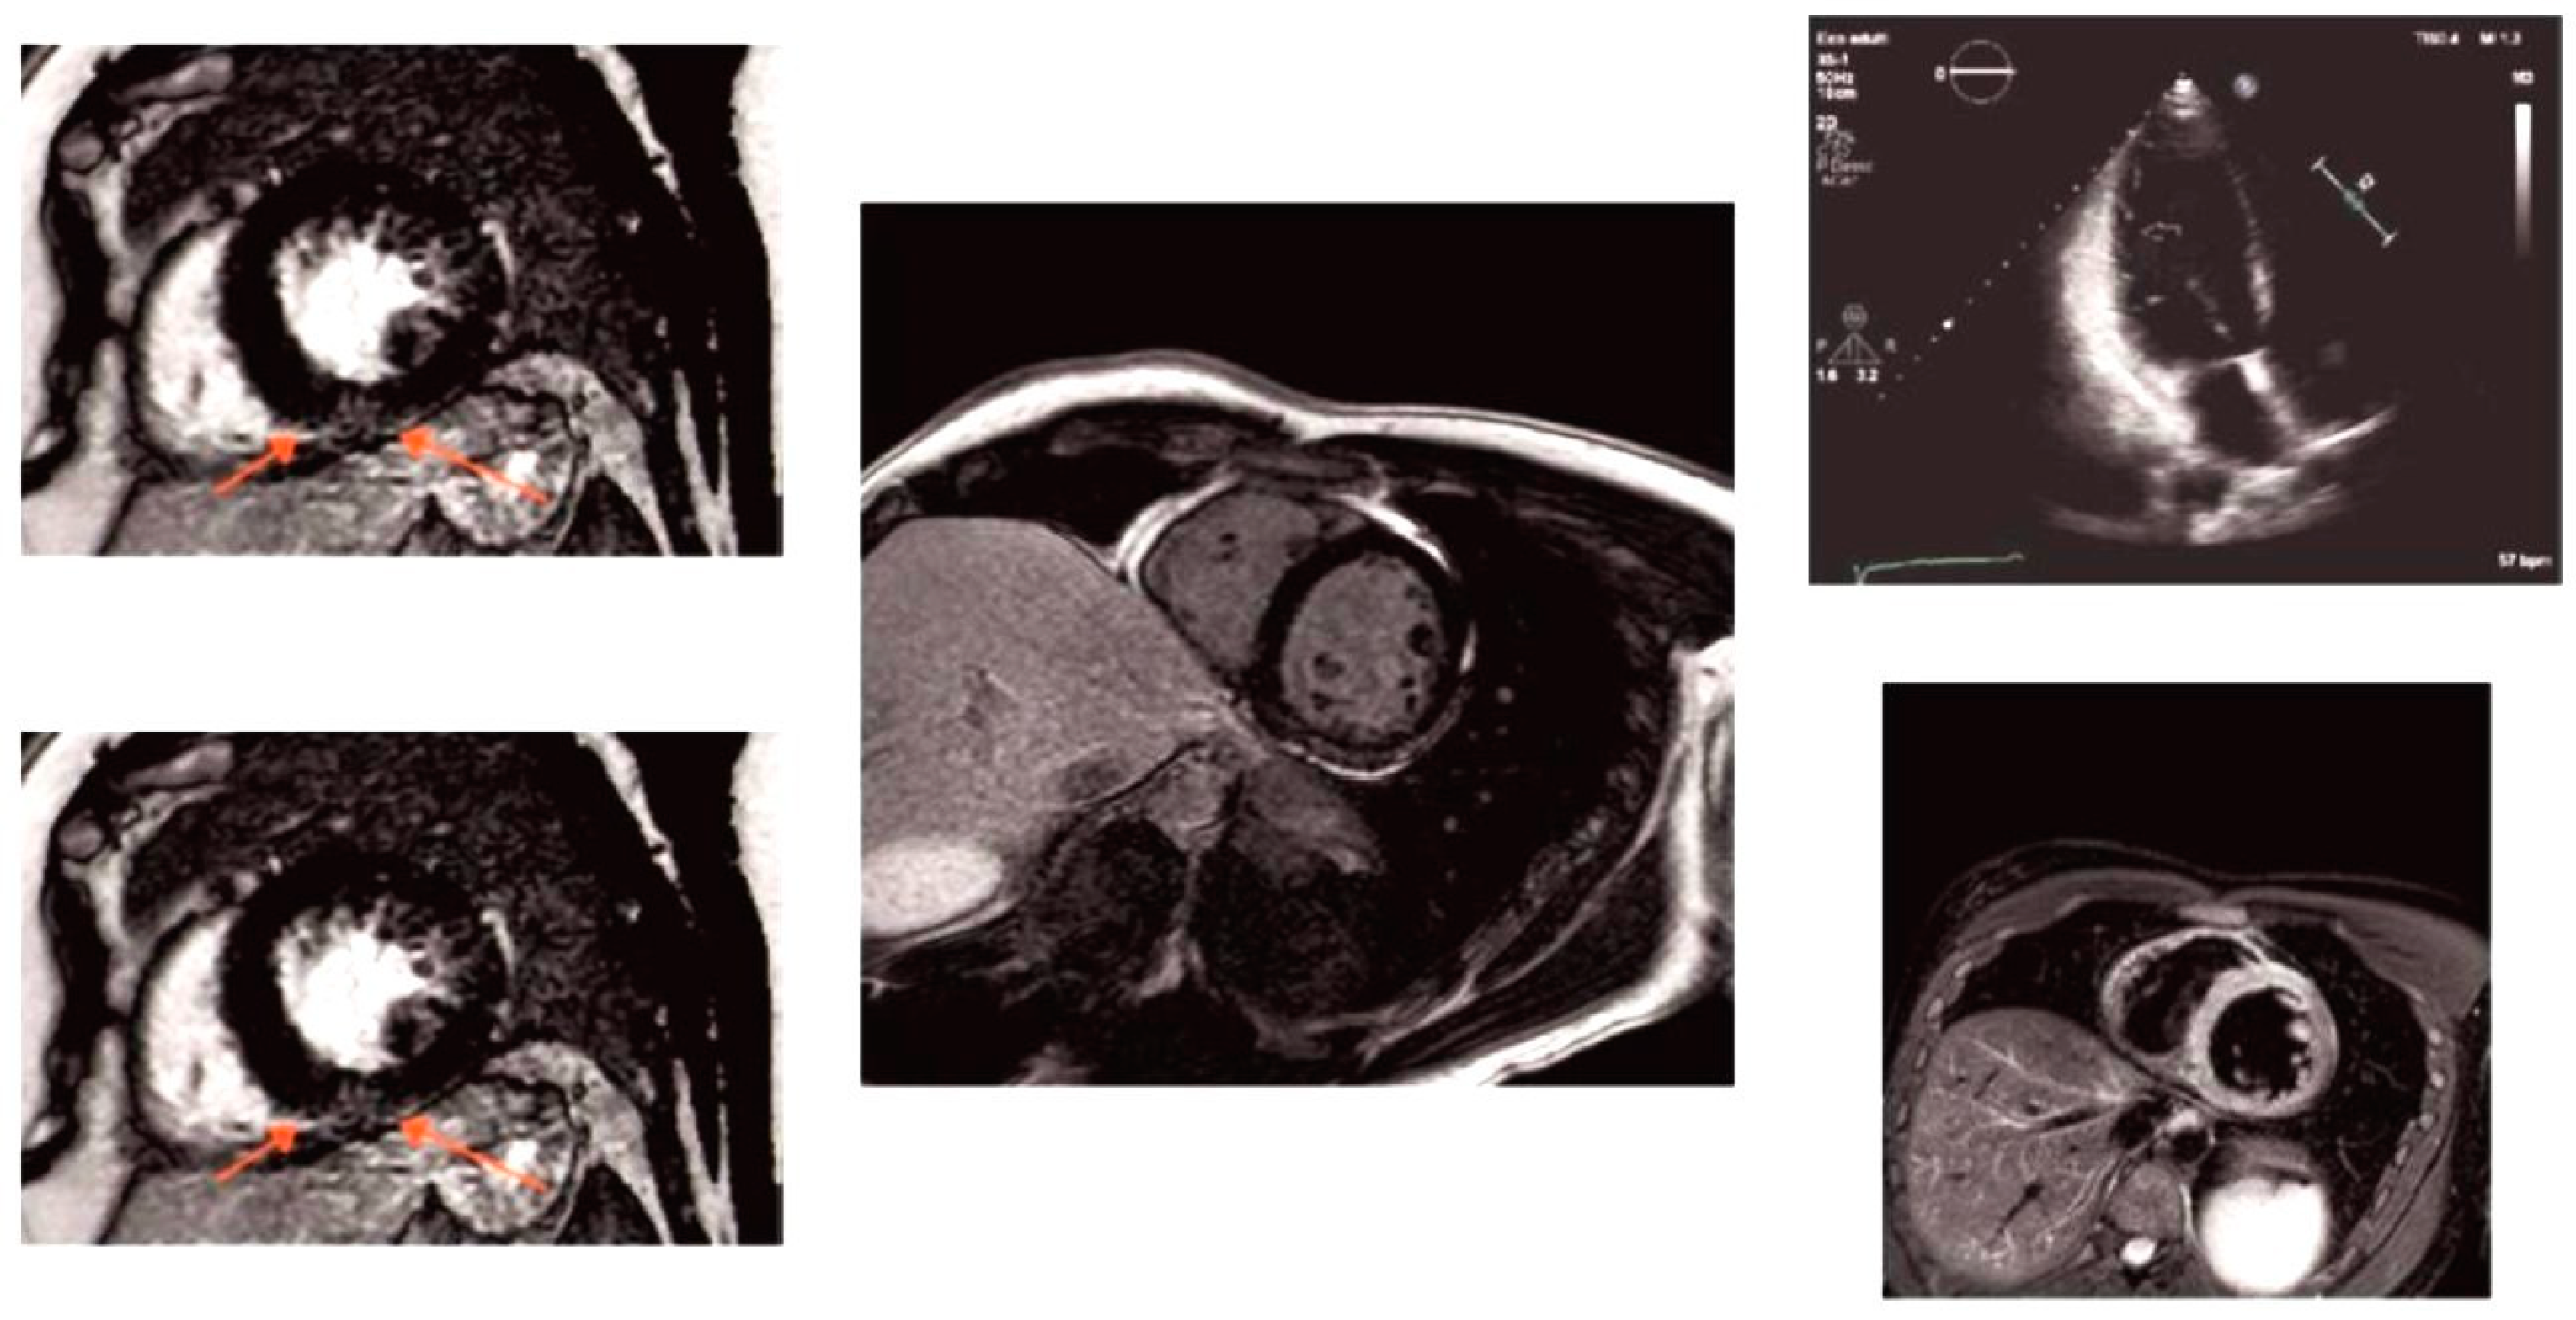

2.3.1. Patient 1

2.3.2. Patient 2